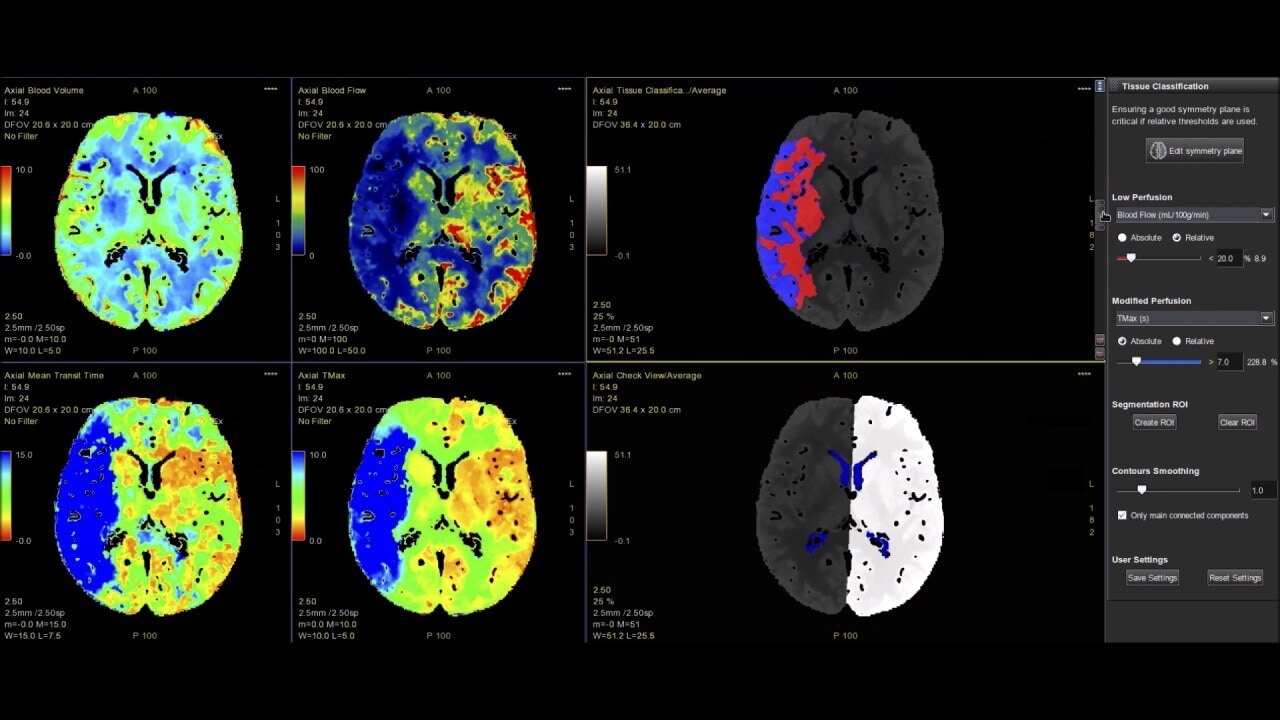

CT Perfusion 4D

Fast, easy-to-use automated software for analyzing CT Perfusion images related to stroke, tumor angiogenesis and dynamic myocardial perfusion.

• Automated generation of all functional maps: Blood Flow, Blood Volume, Mean Transit Time, and Transit Time to IRF Peak (Tmax)

• Tissue Classification enables the visualization of regions that are segmented from absolute or relative values, customizable thresholds and user selectable input maps

• Mismatch volume and ratio are calculated from the modified perfusion volume and low perfusion volume ROIs